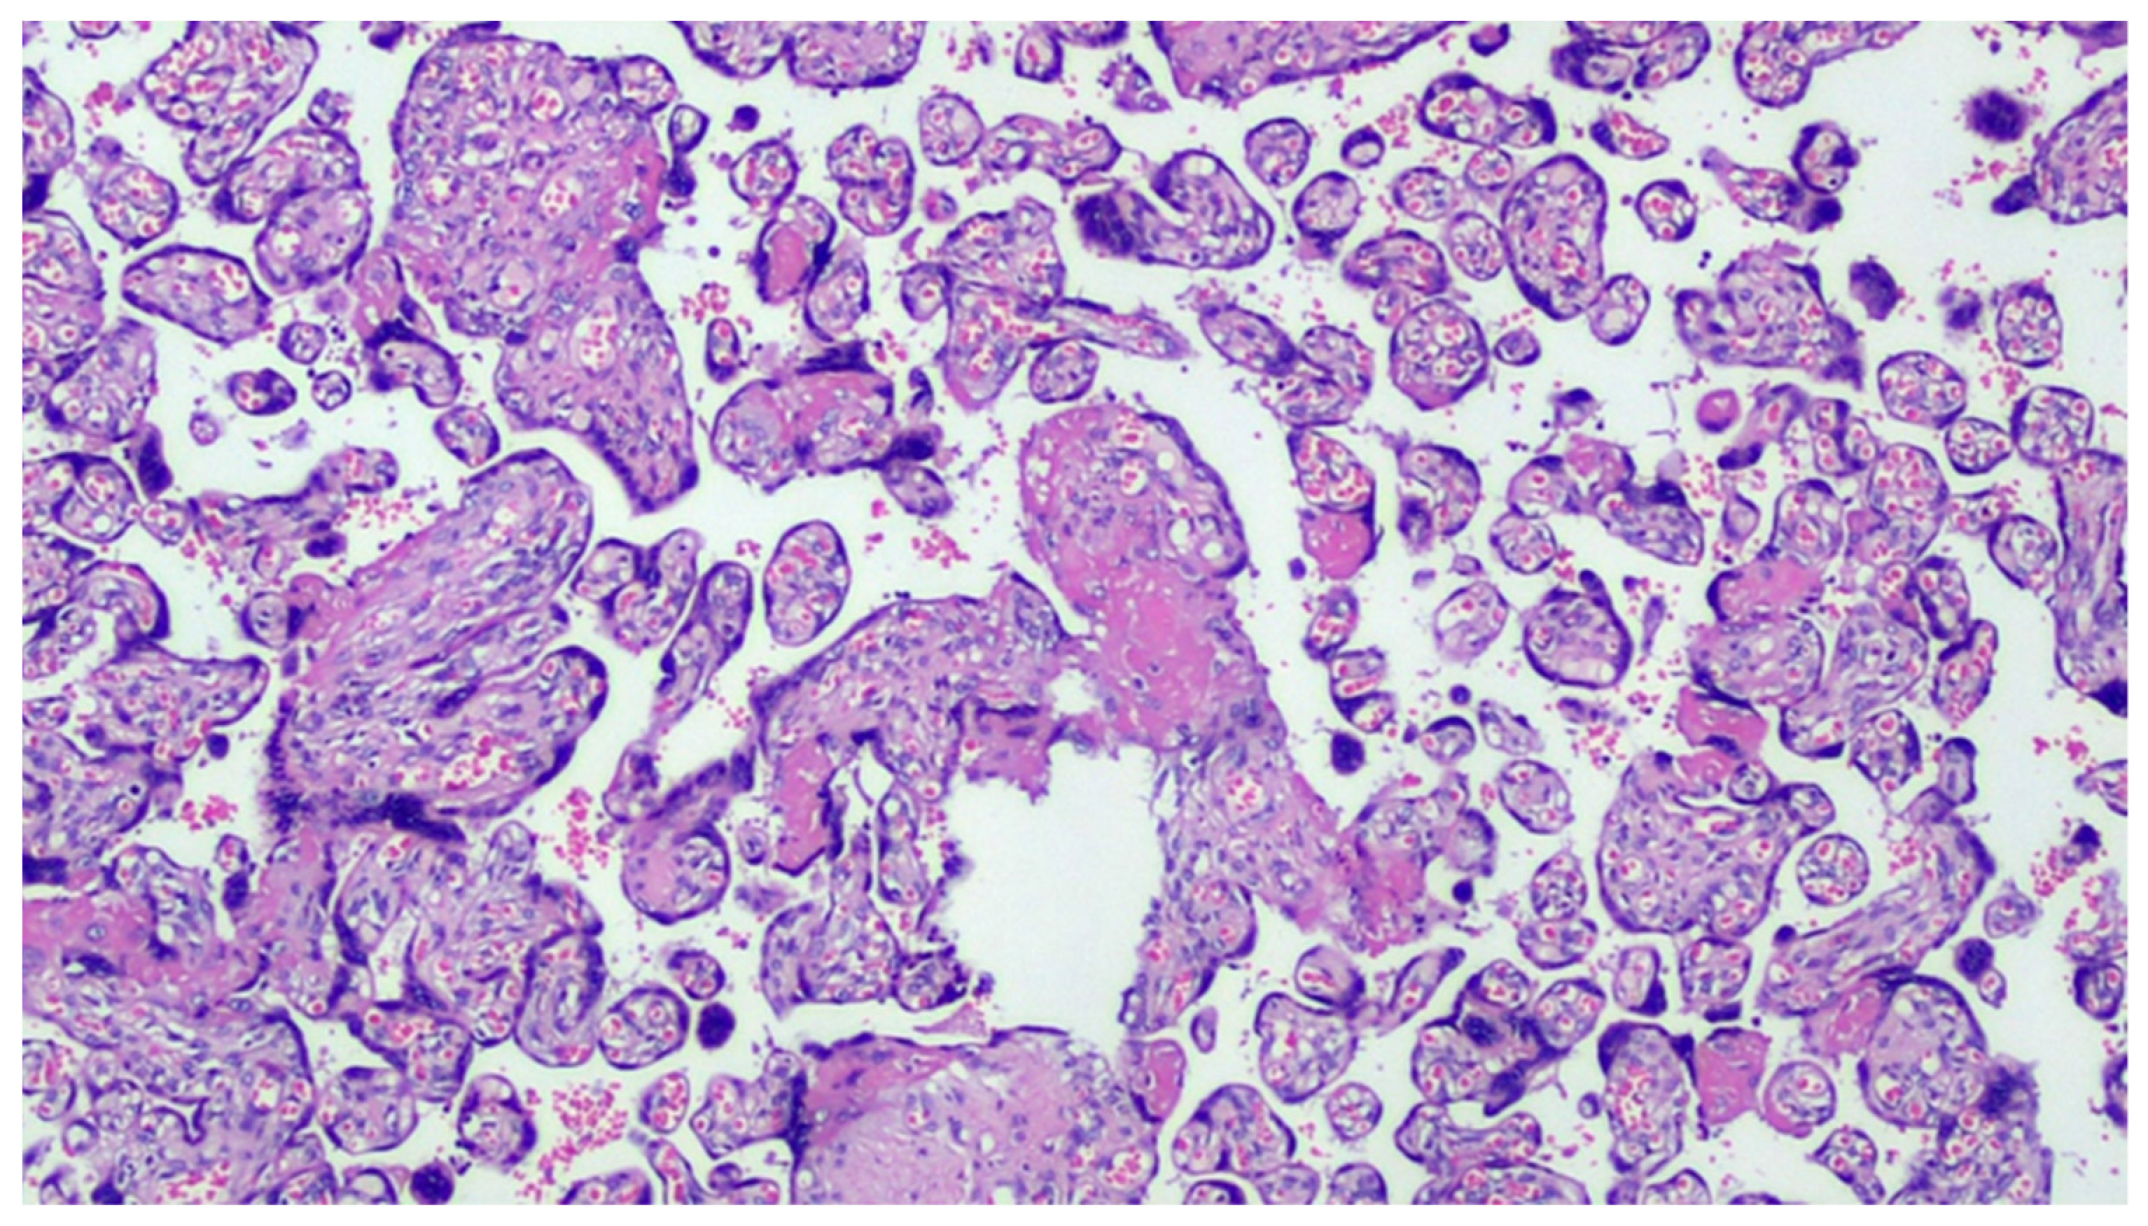

Figure 1.

COVID-19-positive mother placenta. Terminal chorionic villi with poor vascular component (distal hypoplasia of the villi due to early maternal malperfusion) with increased syncytial nodes. Some villi show a deposition of fibrin in the intervillar space with progressive reduction of the villi (H&E, Hematoxylin and Eosin, 100×).

The mean placental weight was not significantly different between the two groups (p = 0.48). No differences in the percentage of maternal vascular malperfusion were observed in the cases compared to controls (54.3% vs. 43.7% p = 0.19), whereas the differences with regard to fetal vascular malperfusion (21.1% vs. 4.2% p < 0.001) were significant. The same applied for decidual arteriopathy (40.9% vs. 1.4% p < 0.0001), decidual inflammation (32.4% vs. 0.7% p < 0.0001), perivillous fibrin deposition (36.6% vs. 3.5% p < 0.0001) and fetal vessel thrombi (22.5% vs. 0.7% p < 0.0001). In contrast, a lower percentage of villous hypervascularization (12.7% vs. 34.5% p < 0.001) was observed in the SARS-CoV-2-positive group compared to controls (Figure 1, Figure 2, Figure 3, Figure 4 and Figure 5). No significant differences in the percentage of terminal villous hyperplasia and chorioamnionitis were observed between the two groups (Table 2). The anti-SARS-CoV-2 spike-S1 glycoprotein antibody’s results were significantly different, with 33/51 cases (65%) of diffuse positivity throughout the examined section and 18/51 cases (35%) of localized positivity, the expression being prevalent in the cytoplasm of the villi trophoblasts. We also observed positivity in 13/51 (25%) cases in the endothelium of the villi capillaries in sites of thrombosis; 14/51 cases (28%) showed positivity in the maternal decidual cells and in the intervillous histiocytes from maternal blood (Figure 6, Figure 7, Figure 8 and Figure 9).